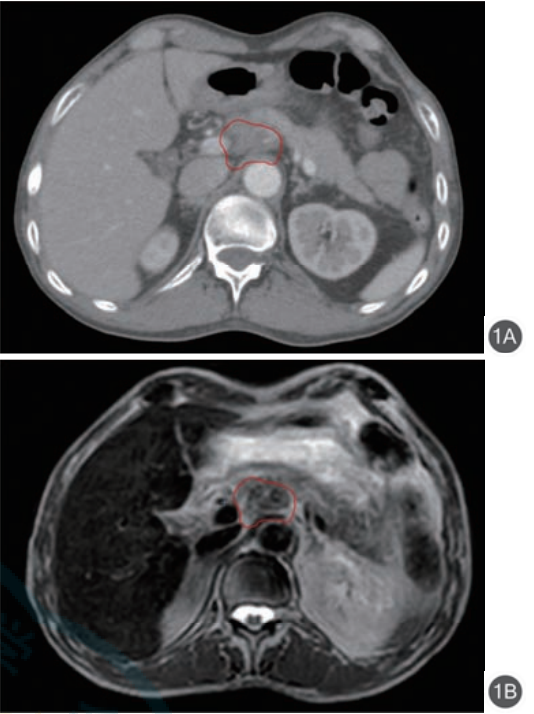

由于磁共振图像显示的是氢原子在人体组织中的密度而不是电子密度,其在软组织成像上有着相比于CT图像更高的对比度与清晰度(图1)。这些优点使其非常适用于治疗软组织区域及器官活动明显的肿瘤,磁共振图像引导放疗(magnetic resonance image guided radiation therapy,MRIgRT)由此成为一项新兴的研究热点,它的出现使得SBRT技术的应用更加安全,其在胰腺癌放疗中有着广阔的应用空间。

注:红线为计划靶区

图1 胰腺癌患者同一横截面下参考计划CT图像(1A)与1.5 T磁共振加速器在线MR图像(1B)的对比